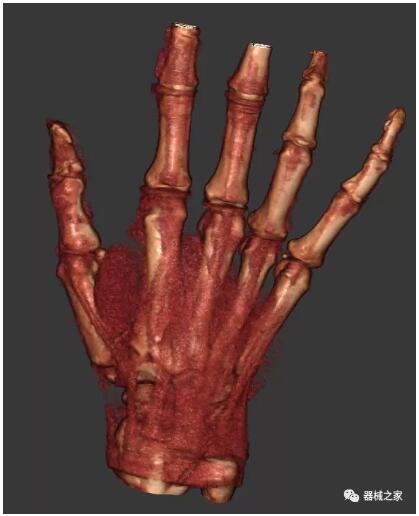

以下是這些“特立獨行”的CT所拍出來的圖像: